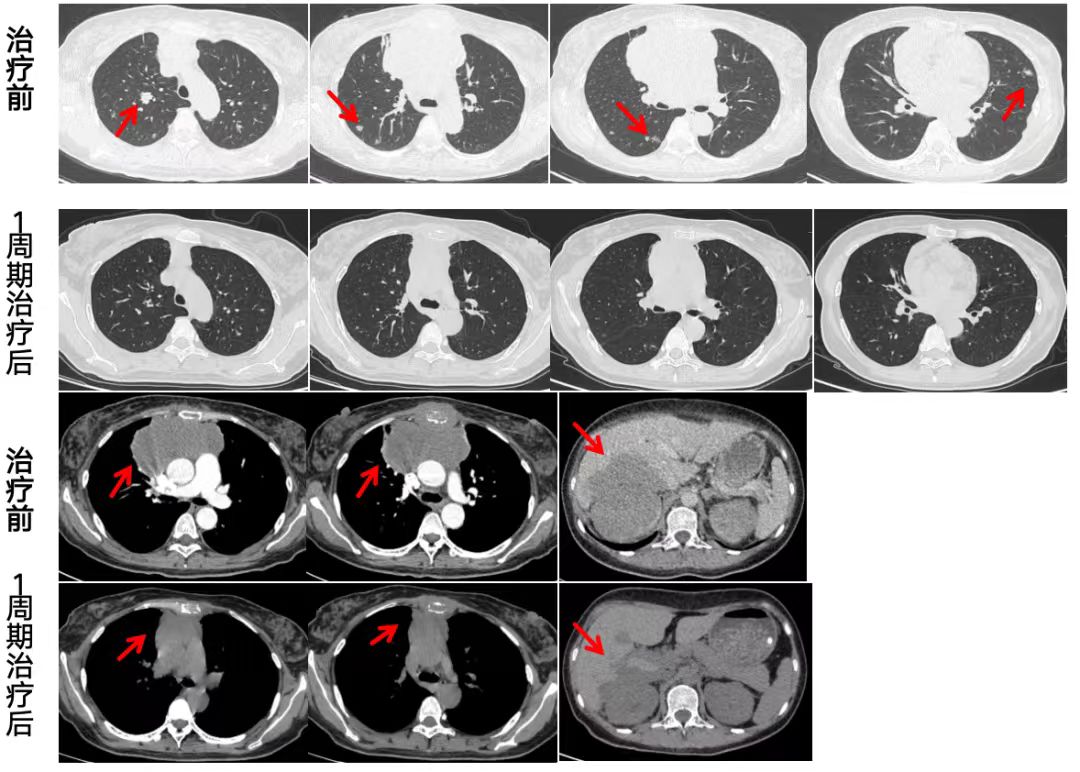

王女士今年42岁,一个月前突发胸痛和腿痛,到他院就诊,被诊断为晚期肿瘤。 病理类型尚未明确之际,王女士的病情急转直下,突发严重急性肾功能不全,血肌酐水平飙升至592.7微摩尔/升,情况危急。 经人推荐,王女士怀着一线希望来到河南省胸科医院寻求救治。肿瘤内科主任李瑞杰接诊了王女士。李瑞杰发现王女士的病情非常复杂:肿瘤全身多发转移,病理类型未明确,同时肾脏几乎停止工作,必须依赖血液透析维持生命。 此时,治疗陷入困境:积极抗肿瘤可能加剧肾损伤,而放弃治疗则会导致病情快速恶化。李瑞杰团队面临严峻挑战。 在等待最终病理检查结果的关键一周内,李瑞杰团队果断采取血液透析替代肾功能的方式,为后续治疗争取时间。 病理检查提示:侵袭性B细胞淋巴瘤。 侵袭性B细胞淋巴瘤是血液系统里一种恶性程度高、发展快的肿瘤,它起源于B淋巴细胞,特点是肿瘤细胞增殖迅速、容易侵犯多个器官,早期症状可能不明显,但进展后可能出现淋巴结肿大、乏力、发热、盗汗、腹胀、腹痛等症状。 侵袭性B细胞淋巴瘤与肾衰竭常相互关联。肿瘤细胞可直接浸润肾脏、压迫尿路,或引发高尿酸血症、高钙血症等代谢问题,损伤肾功能。 “如何能在控制肿瘤的同时保护残存的肾功能,并确保药物不被透析清除,是治疗的关键。”李瑞杰在多学科专家会诊时说。 经过综合评估,李瑞杰团队为王女士制定了个体化治疗策略:在间断血液透析的支持下,谨慎使用新型靶向药物组合,并依据肾功能动态调整剂量,力求实现抗肿瘤治疗与肾功能保护的双重目标。 令人欣慰的是,在医患双方的共同努力下,第一个周期治疗后,王女士的肿瘤明显缩小,血肌酐水平明显下降,肾功能逐步恢复。她成功脱离了血液透析,摆脱了对“人工肾”的依赖。目前,王女士病情稳定,已进入后续治疗阶段。 对于这个病例,李瑞杰说,这次治疗不仅控制了肿瘤进展,更逆转了患者的急性肾衰竭结局,说明现代肿瘤治疗已能为患者制定高度个体化的方案,即使在病情复杂的情况下也能取得成功。 (作者供职于河南省胸科医院)